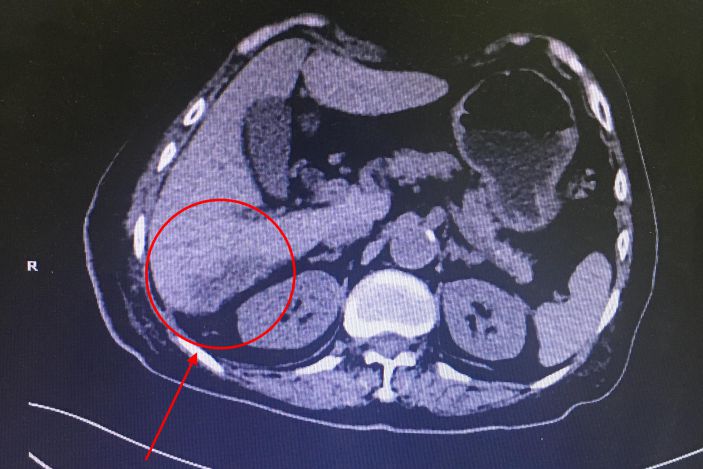

經CT檢查發現患者肝右葉S5、S6、S7段多發膿腫,病竈最大的達6.0*4.2cm,結腸肝曲周圍炎性滲出。據了解,肝膿腫是肝髒化膿性病變,若不積極治療,死亡率達10%-30%。

許婆婆,74歲,流沙人,反複上腹部疼痛,伴有發熱1個月。在外院就診,但一直得不到很好的診治。病情反複,高熱39℃,日漸消瘦。3月25日轉至我院就診,收住外一科。

△術前病竈部位

經CT檢查發現患者肝右葉S5、S6、S7段多發膿腫,病竈最大的達6.0*4.2cm,結腸肝曲周圍炎性滲出。據了解,肝膿腫是肝髒化膿性病變,若不積極治療,死亡率達10%-30%。